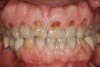

Figure 2  Asymmetric tooth wear in a bruxism triad patient as a result of friction from bruxing, poor salivary lubrication as a byproduct of medication, and roughened surfaces created as a result of erosive reflux.

Figure 2